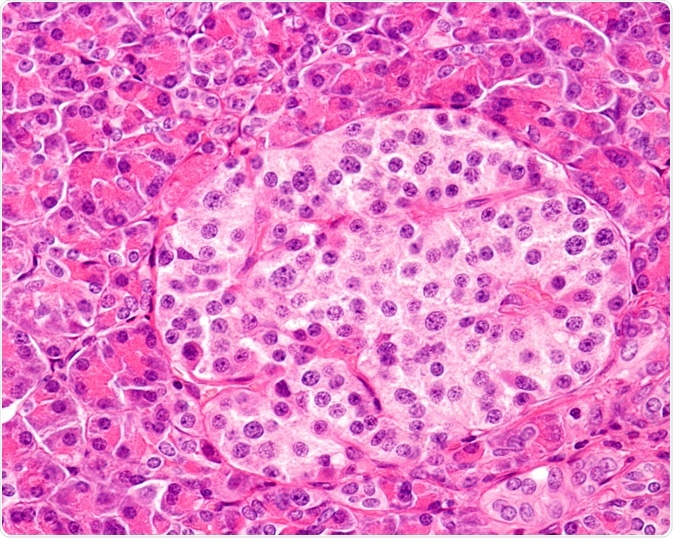

Image Credit: Jose Luis Calvo/Shutterstock.com

One such disease is type I diabetes, which develops as a result of immune cell-mediated destruction of the pancreatic B cells.

In encapsulated islet therapy, beta cells in patients with T1DM are replaced with immunoprotective islets derived from healthy donors. These donor islets are delivered inside selectively permeable alginate hydrogel microcapsules.